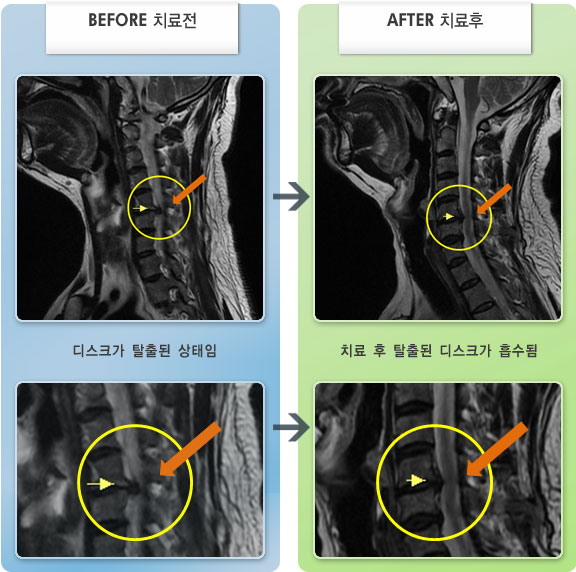

Before

After

목과 왼쪽 팔에서 1,2번째 손가락까지 저리고 당기는 통증

2012.05.07 ~ 2013.03.13